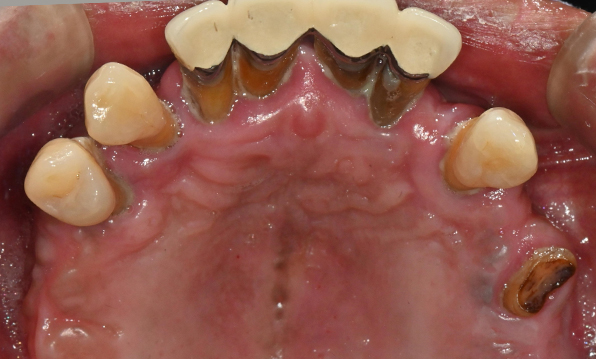

Case 02

Before After